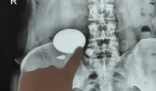

近期,湖北的吴女士因腰部剧痛难忍前往医院,本以为是小毛病,结果医生在她体内发现了一个酷似鹅蛋的东西,确认为结石。除了这颗“鹅蛋”结石外,吴女士右肾下盏还散布着多颗结石,并伴有重度积水。医生判断,这颗结石如果不及时处理,严重时可致肾功能完全丧失。

通过一个半小时的手术,吴女士体内的鹅蛋结石和其他小结石被粉碎取出。这样一颗鹅蛋结石,即使在专科医生眼里也非常罕见,它是如何形成的呢?据医生追溯既往病史后得知,吴女士不太喜欢喝水,每天饮水总量仅有1000毫升左右。这导致她体内尿液浓缩,里面的草酸、尿酸结晶、沉积,最后形成了一颗巨大结石。